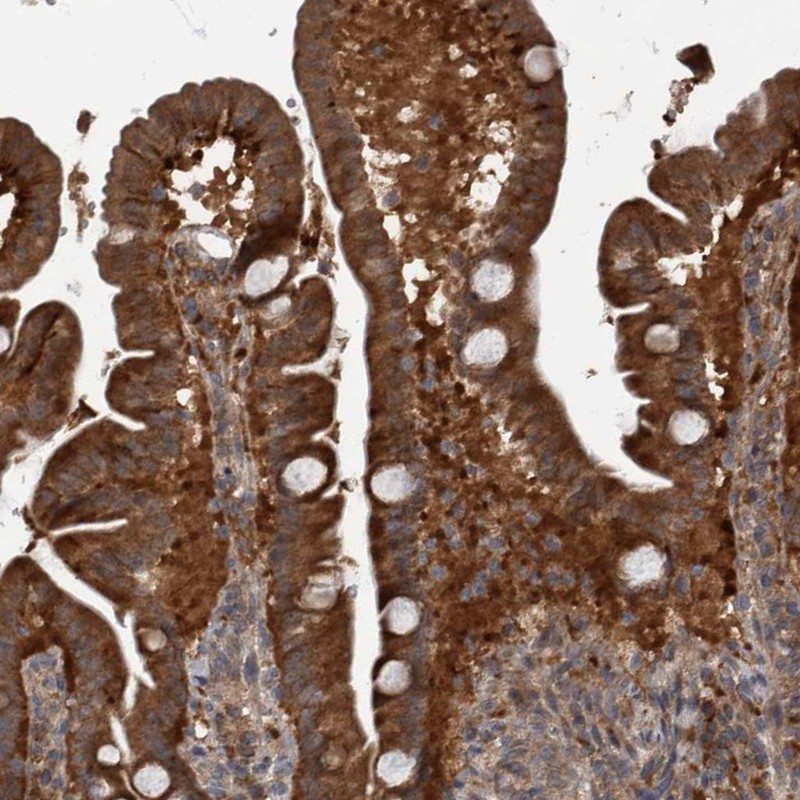

Immunohistochemical staining of human duodenum shows strong cytoplasmic positivity in glandular cells.